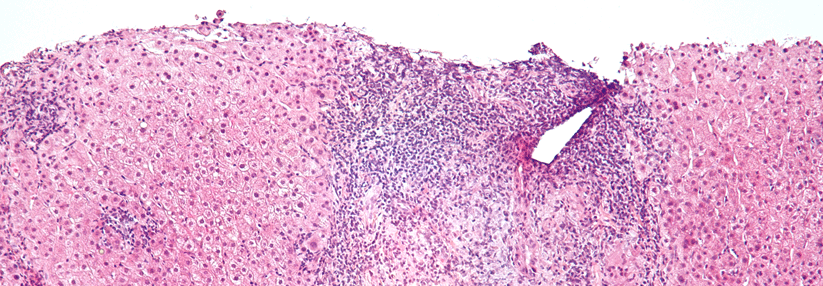

Die primär biliäre Cholangitis (PBC) ist mit einem Anteil von 80–90 % vor allem eine Erkrankung von Frauen, erklärte Prof. Dr. Christoph Schram von der Medizinischen Klinik I an der Universitätsklinik HH-Eppendorf. Die Prävalenz liegt bei 40/100.000 und das mittlere Erkrankungsalter bei 50 bis 60 Jahren. Die Diagnose kann gestellt werden, wenn zwei der folgenden drei Kriterien erfüllt sind:

• chronische Cholestase

• antimitochondriale Antikörper (AMA, bei über 90 % positiv) oder typische antinukleäre Antikörper (ANA, etwa 70 % der AMA-negativen Patienten)

• typische Histologie